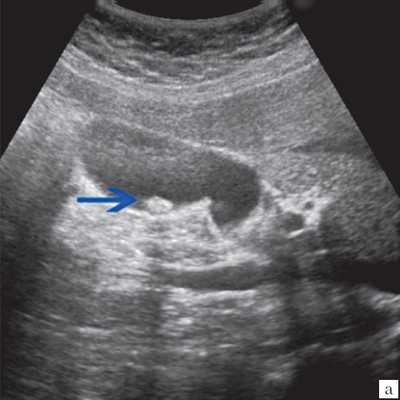

Ультрасонография является эффективным средством выявления полиповидной формы холестероза 8. Традиционной считается следующая сонографическая характеристика холестериновых полипов: неподвижные гиперэхогенные структуры, которые не дают акустической тени и прикрепляются к стенке желчного пузыря. Контуры таких образований, как правило, ровные, а размеры таких образований различны, чаще не превышают 10 мм (рис. 2).

a) Одиночный полип в желчном пузыре (гиперэхогенное пристеночное неподвижное образование, с ровными контурами, без акустической тени).

б) Одиночный полип в желчном пузыре.

в) Полиповидно-сетчатая форма холестероза, полипы размерами до 5 мм, повышенной эхогенности.

г) Одиночный полип в желчном пузыре.